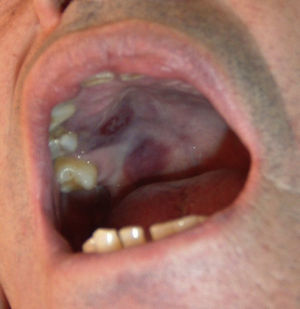

Quince meses después del diagnóstico, se observó la aparición de lesiones purpúricas en el paladar blando primero y, posteriormente, en el dorso del pie izquierdo, que se biopsiaron. El estudio anatomopatológico fue compatible con SK (fig. 2) y el estudio inmunohistoquímico resultó positivo para virus herpes humano tipo 8 (VHH-8). Los estudios complementarios descartaron afectación visceral. Se repitió la serología para VIH, que fue negativa. En marzo del 2009, el paciente inició tratamiento con quimioterapia (doxorubicina), reduciéndose la dosis de prednisona y consiguiéndose la mejoría de las lesiones cutáneas. En la TC torácica de enero del 2009 se observaron múltiples imágenes nodulares pulmonares que no aparecían en estudios previos, por lo que se realizó biopsia pulmonar abierta, con el resultado de fibrosis intersticial inespecífica con cambios enfisematosos y alteraciones vasculares en pequeñas arteriolas. Ante el resultado de la biopsia pulmonar y el deterioro funcional del paciente, fue necesario aumentar la dosis de esteroides y se decidió añadir ciclosporina al tratamiento, sin que con ello se modificase el aspecto radiológico de las lesiones pulmonares, aunque se produjo mejoría en la clínica y en la espirometría. Posteriormente, a principios del año 2012, el paciente presentó recidiva del SK, con aumento de lesiones cutáneas en los miembros inferiores, por lo que se administró nuevamente quimioterapia con betaxolol. Cabe destacar que todos los intentos por disminuir el tratamiento esteroideo por debajo de 7,5mg/día han resultado infructuosos por empeoramiento de la clínica respiratoria.